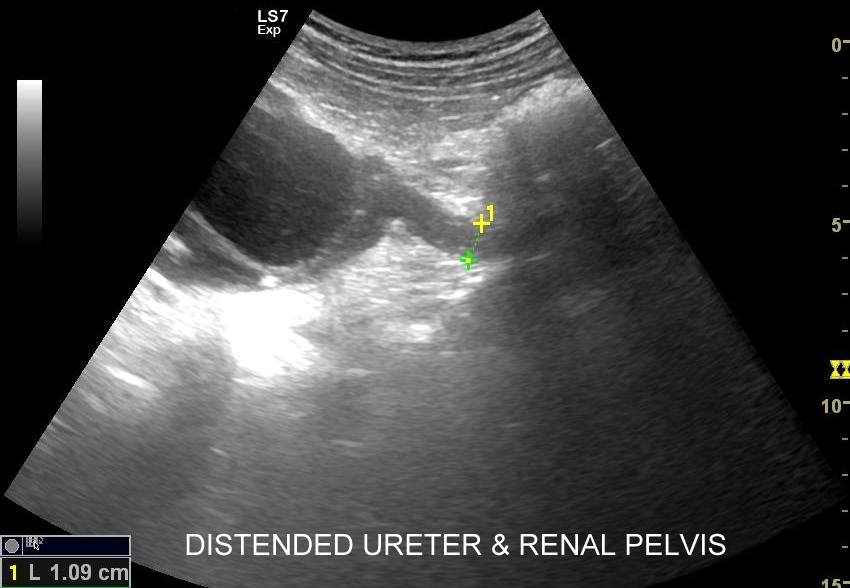

Objawy kolki nerkowej wynikają z mechanicznego drażnienia i wtórnego ranienia ścian moczowodu w trakcie przemieszczania się kamienia, a ich lokalizacja zależy od miejsca, w którym aktualnie złóg się znajduje. Najczęściej może on utknąć w naturalnych zagięciach i przewężeniach moczowodu, tj. na złączu miedniczkowo-moczowodowym, na skrzyżowaniu moczowodu z naczyniami biodrowymi oraz przy pęcherzu moczowym. W omawianych warunkach dominują zasadniczo bóle o charakterze ostrym. Druga przyczyna objawów związanych z kolką nerkową wynika z zastoju moczu oraz podwyższonego ciśnienia w układzie kielichowo-miedniczkowym; w tym wypadku dominują bóle tępe.

Badania obrazowe służące wykrywaniu kamicy moczowej to badanie RTG, CT, lecz przede wszystkim badanie USG. W badaniu USG nerek w prezentacji B kamica nerkowa widoczna jest w sytuacji, gdy złogi są odpowiednio uwapnione, odpowiednio duże oraz nie zlewają się z zatoką tłuszczową miedniczki nerki. Zasadniczo złogi w trybie B będą widoczne wyraźniej, gdy położone są w miąższu nerki; z kolei w miedniczce nerkowej, gdy są na tyle duże, że dają artefakt cienia. Czasem w celu uwidocznienia złogu przydatne jest wyłączenie wspomagania typu x-beam.